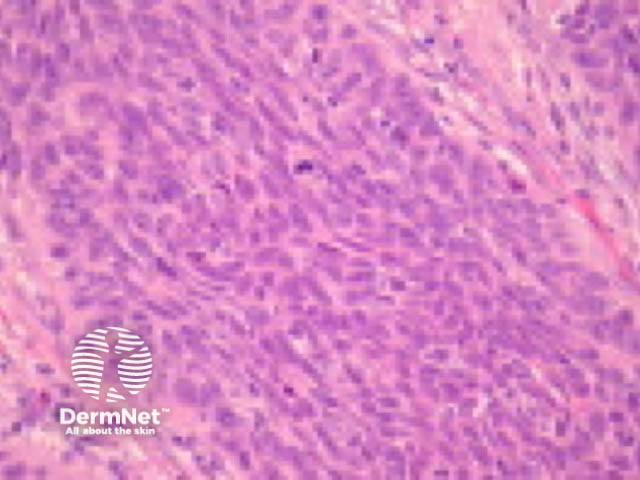

Typically SCC is graded as:

Grading of SCC depends on how easy it is to recognise the characteristics of squamous epithelium (eg. intracellular bridges, keratinisation), pleomorphism and mitotic activity. There is considerable inter-observer variation in grading SCC.

Figure 3